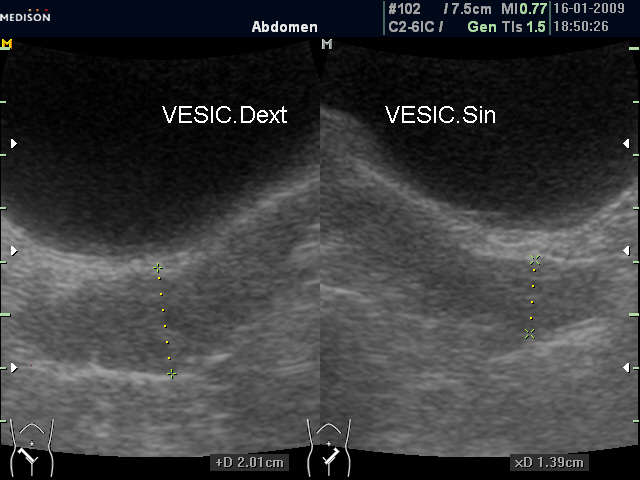

Асимметрия СП (ТА УЗИ)